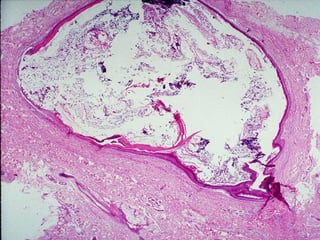

• #40 Epidermal inclusion cyst, the overlying skin looks normal.

• #41 Epidermal inclusion cyst